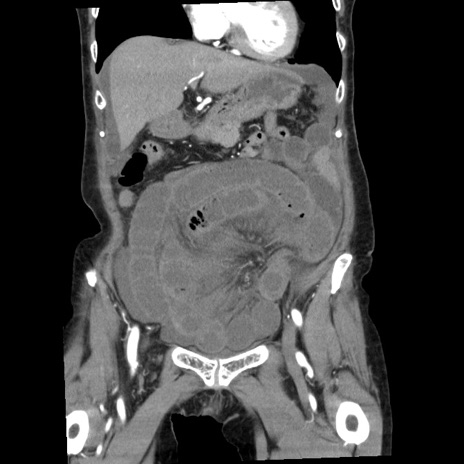

症例1(冠状断像)

【症例】80歳代女性

【主訴】腹痛

【現病歴】8時間前から腹痛あり来院。

【既往歴】糖尿病、脂質異常症、子宮体癌にて子宮全摘術

【身体所見】意識清明・会話良好だが腹痛で苦悶様、全腹部にわたって反跳痛と圧痛あり

【データ】WBC 13600、CRP 0.14、LDH 224、CK 90